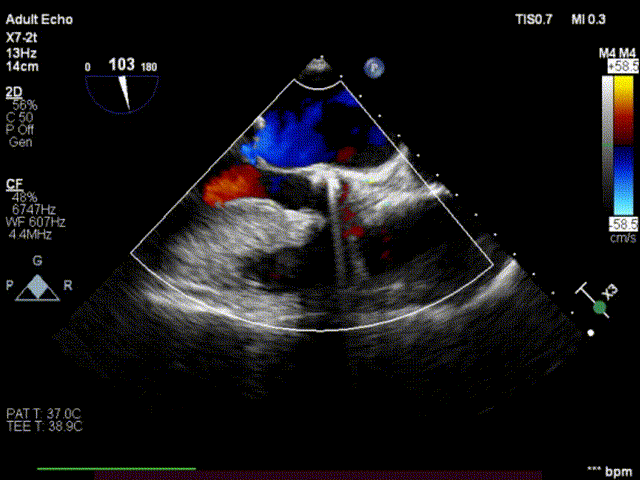

术前心超

术后心超

术中使用22mm杰成经血管介入瓣膜,顺利完成手术,经超声评估患者跨瓣压差等指标较术前明显改善。患者恢复状况良好,术后第一天便顺利出院。

术后反流改善,无瓣周漏

使用28mm杰成经血管介入瓣膜,顺利完成手术,术后主动脉瓣反流情况消失。患者术后第二天便顺利出院。